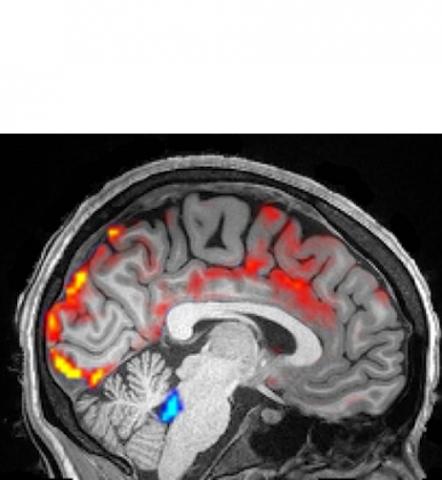

Que se passe-t-il la nuit dans le cerveau ? L’étude de Boston révèle que la nuit, durant le sommeil, les neurones se taisent, et, quelques secondes plus tard, le sang irrigue notre cerveau (en rouge sur visuel), puis c’est le tour du liquide céphalo-rachidien (LCR- en bleu sur le visuel) qui s’infiltre dans le cerveau en ondes pulsatoires rythmées. « Nous savons depuis longtemps qu'il existe des ondes électriques d'activité dans les neurones », commente l’un des auteurs, Laura Lewis, professeur de génie biomédical, « mais nous ignorions qu'il y avait des vagues dans le LCR, aussi ».

Un modèle dynamique électrophysiologique, hémodynamique et du LCR : Les chercheurs ont utilisé une technique de neuroimagerie accélérée pour mesurer la dynamique physiologique et neurale dans le cerveau humain de 13 participants âgés de 23 à 33 ans. Ils ont pu reconstituer un schéma cohérent et dynamique, à la fois électrophysiologique, hémodynamique et du LCR, qui apparaît pendant le sommeil à mouvements oculaires non rapides. Des ondes neurales lentes sont suivies par des oscillations hémodynamiques, elles-mêmes couplées au flux de LCR. Ces résultats démontrent que le cerveau endormi présente des ondes de flux de LCR à une échelle macroscopique et que cette dynamique du LCR est liée à des rythmes neuronaux et hémodynamiques.